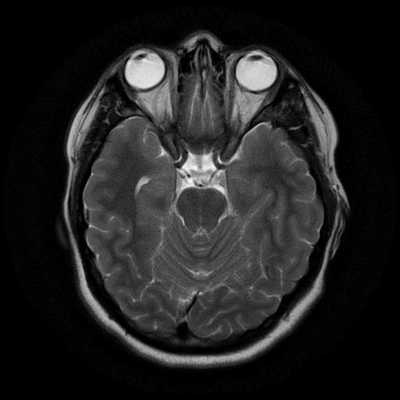

Как выглядит снимок МРТ головного мозга

Классический пример МРТ снимков головного мозга показан на рисунках ниже. Магнитно-резонансная томография выполняется в поперечной (или аксиальной - рисунок снизу) и продольной (или сагиттальной — рисунок сверху) плоскостях.

Исследование выполняется в нескольких режимах. Основные из них Т1 и Т2. Изображения, полученные в данных режимах, часто также называют Т1-взвешенными или Т2-взвешенными снимками. Изображения, показанные выше, сделаны в Т1-режиме.

Главное отличие этих режимов - в том, как на снимках отображается жидкость и воздух. В Т1 режиме ткани, содержащие большое количество воды, имеют более темную окраску, в то время как в Т2 режиме они яркие, светлые. Это легко понять, посмотрев на снимки выше - глазные яблоки визуализируются в виде светлых парных округлых образований с одной стороны яркие и светлые, с другой - темные. Следовательно, снимок справа сделан в Т1 режиме, снимок слева - в Т2. Также существует разница в том, как в этих режимах отображается серое вещество головного мозга. В Т2 режиме оно светлее, чем белое вещество.